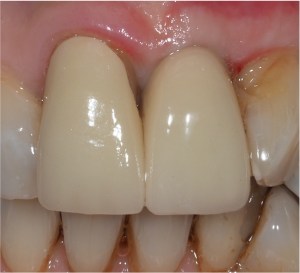

Single implant crowns

Single implant crowns are an excellent way to replace missing teeth. They do not damage the neighbouring teeth and last for a long period of time. These are usually screw retained to allow repair/replacement if there are any maintenance issues.